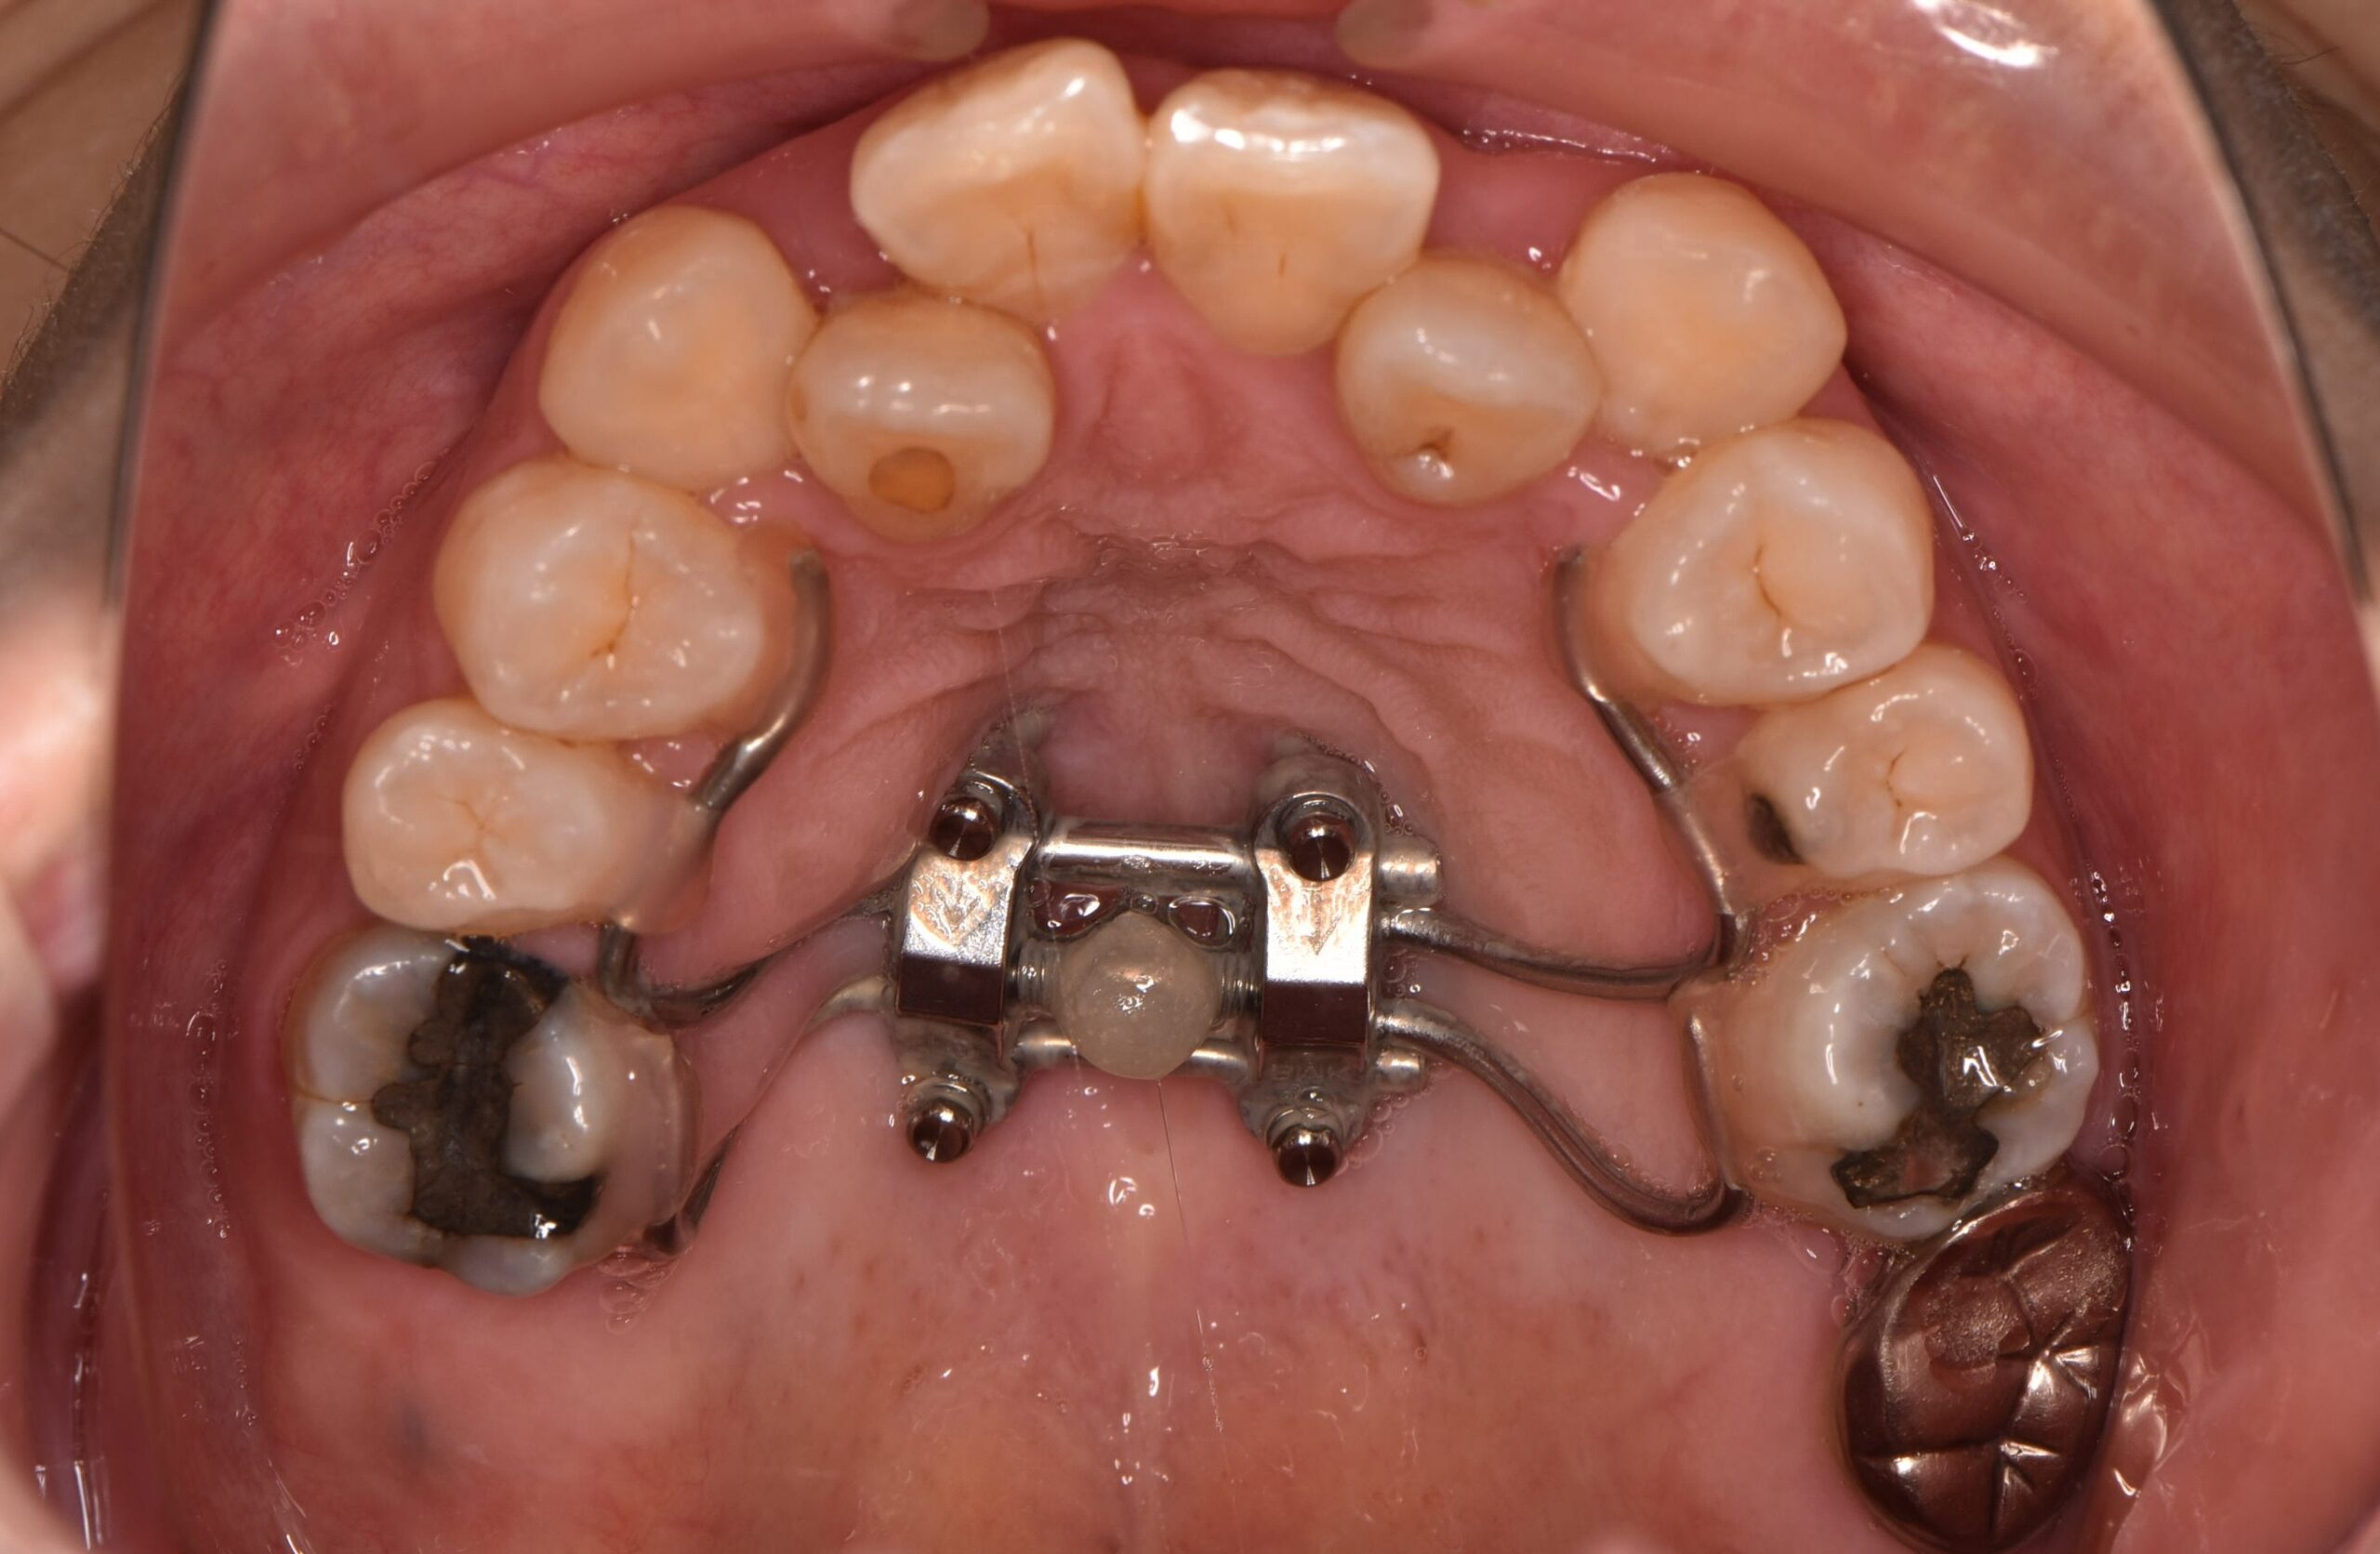

なおこ先生プロデュース 矯正用加熱振動装置。なおこ先生プロデュース 矯正用加熱振動装置 大人の矯正治療について。なおこ先生プロデュース 矯正用加熱振動装置 大人の矯正治療について。なおこ先生プロデュース矯正用加熱振動装置数回使用しましたがサイズが合わなく出品します。なおこ先生も動画でお伝えしておりましたが、振動によって矯正スピードアップを期待できる機器です。【内容】マウスピース、操作部(本体)、接続コード、取扱説明書●単4アルカリ乾電池×4本が必要です(内蔵してお届けします)【使用上の注意】次の方は使用しないでください。・口内の感覚が敏感な方・口腔または歯周手術の直後や治療中の方・口腔内に気になる症状(治療中の歯、不安定な入れ歯)がある方・歯ぐきからの出血が続く、または大量の出血がある方。矯正】上あごを広げる魔法の装置【固定式拡大装置】とは?? | ごとう。消毒済みです。【美品】AGE-R AIR SHOT(エアショット)。JOYトレ バーンコア。マウスピース矯正やワイヤー矯正をしたまま、矯正用加熱振動装置のマウスピースをくわえて、ご使用いただけます。大幅値下げ!パルティール シュアラインa(遠赤外線マット)。【パナソニック】バイタリフトかっさ EH-SP85-K。または使用を歯科医にご相談ください。リファ 4カラット(箱開封のみ)